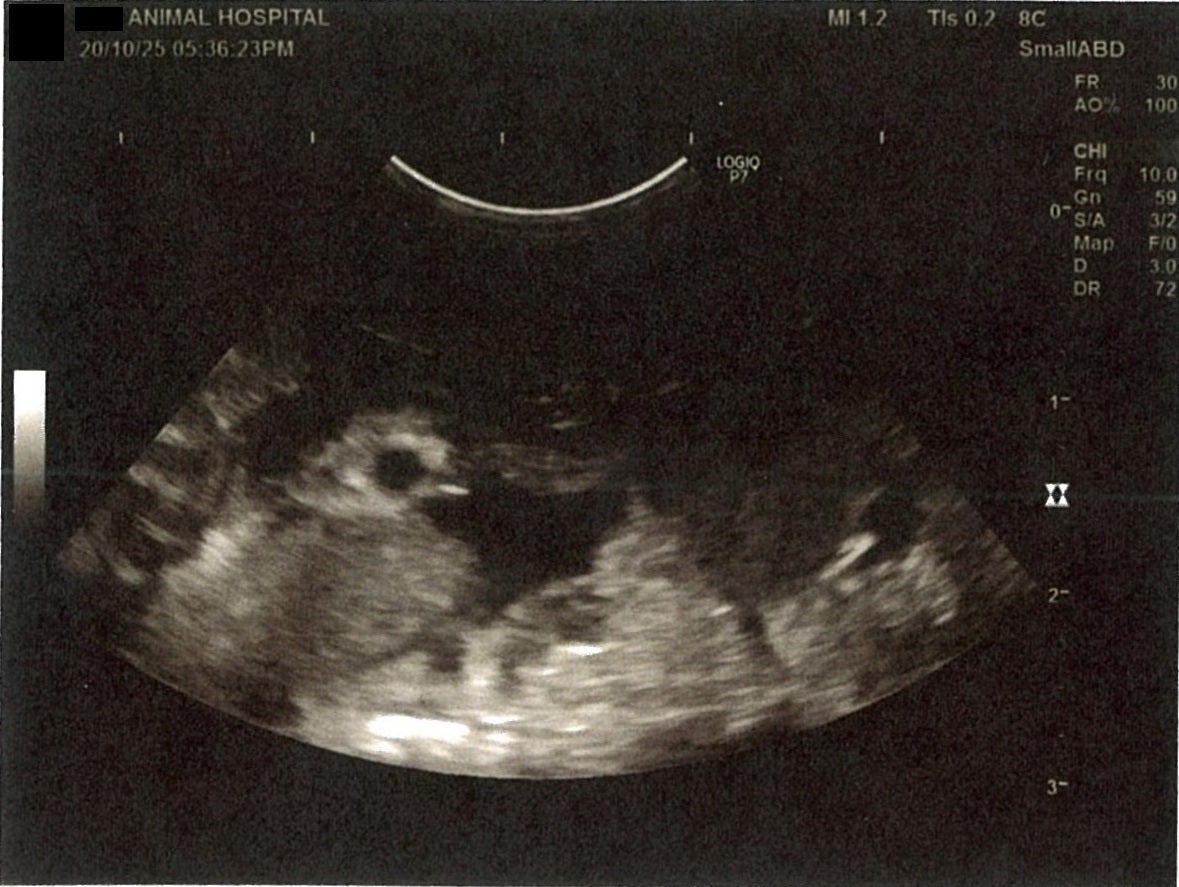

《心臓周りの胸部以外の全ての腹部で腹水がみられるとの診断です》

大網という部分で内臓を包む膜のようなものです。その周りに腹水が溜まっています。

膵臓周りに腹水が確認できるエコー写真